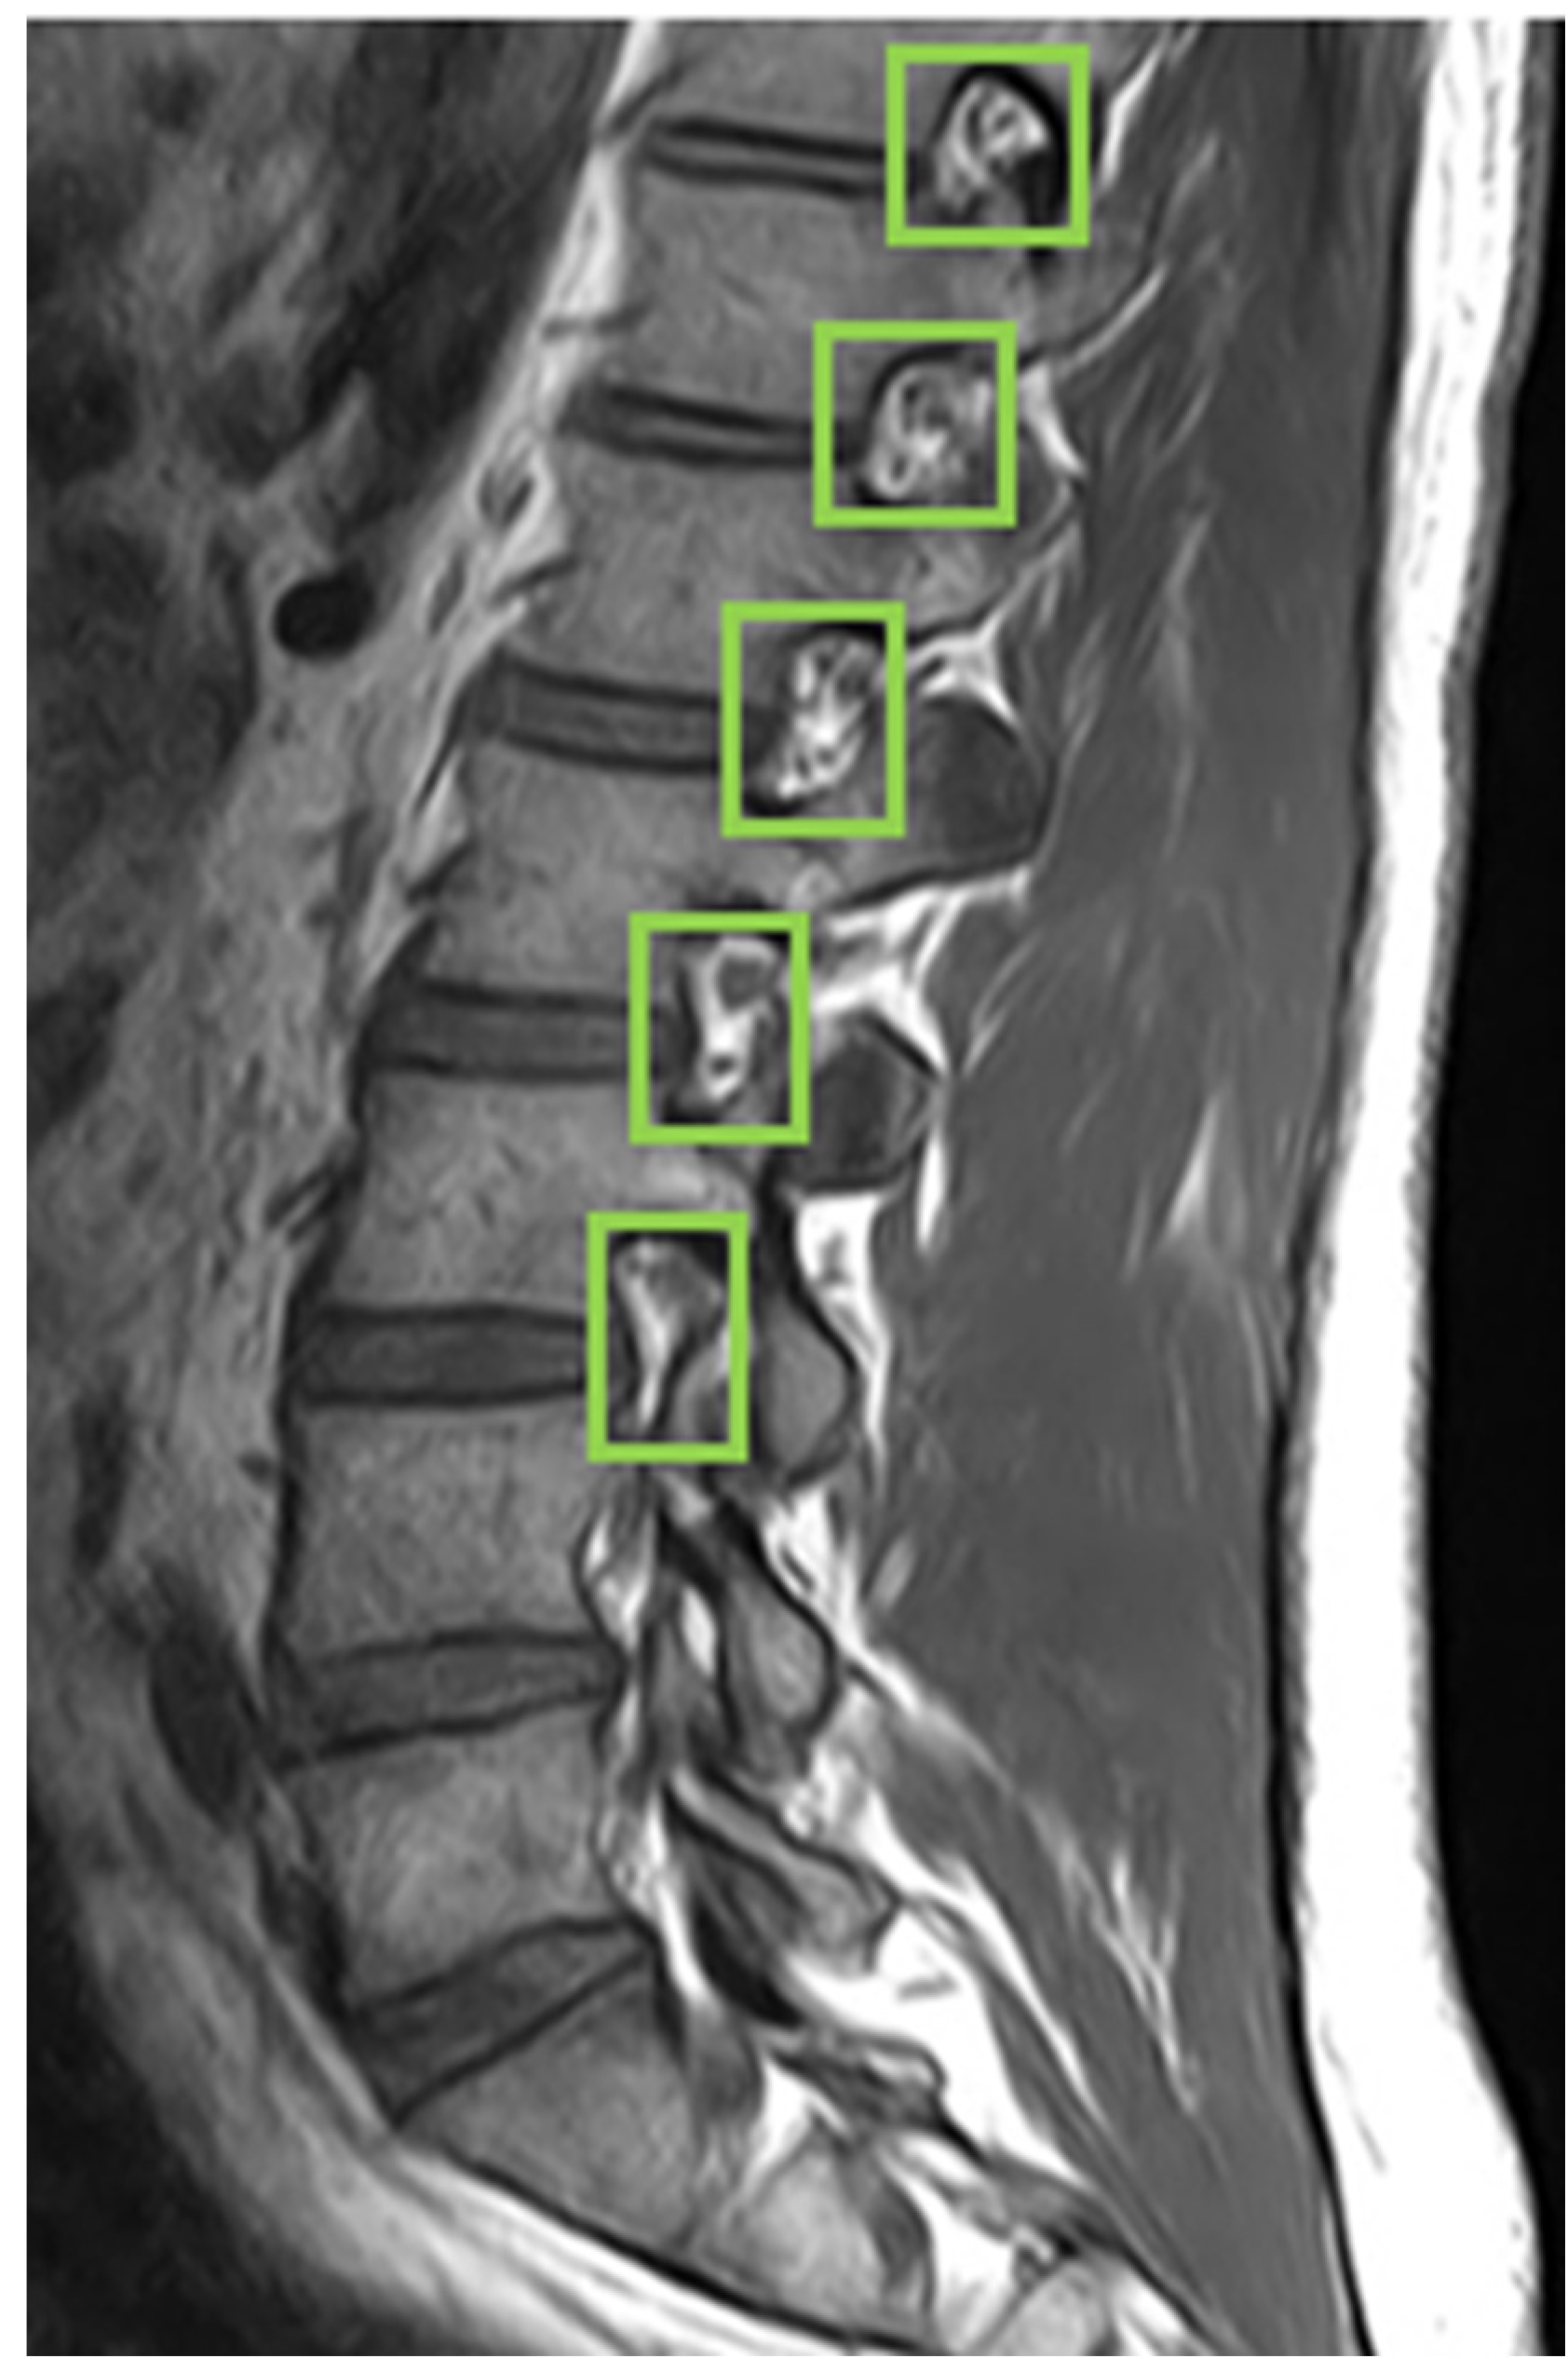

The labeling work is completed using LabelImg, an image labeling tool that is widely used for object labeling. Image preprocessing for the intervertebral foramen dataset, which includes 40 different subjects, involves handling variations in the aspect size of each MRI image. We resize each image to 416 × 416 pixels to standardize the dataset. Additionally, we apply data augmentation to the dataset. Proper data augmentation helps prevent overfitting during training. Specifically, we enhance the original 80 MRI images by generating an additional 80 images through random rotations, hue adjustments, and brightness modifications.

First, we used LabelImg software version v1.8.1 (https://github.com/HumanSignal/labelImg/releases, accessed on 11 February 2023) to delineate the rectangular region of the intervertebral foramen. The annotations were made in YOLO format, with the intervertebral foramen as the sole labeled class. Figure 6 shows an example of a light-green-colored annotated intervertebral foramen MRI image.

Figure 6. Use LabelImg tool to annotate intervertebral foramen MRI image as green boxes.